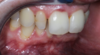

Cas clinique 4 : pose de facettes céramiques sur les incisives latérales

Anomalie de proportion des dents

Anomalie de proportion des dents. Cas clinique 4 : pose de facettes céramiques sur les incisives latérales pour l'esthétique.